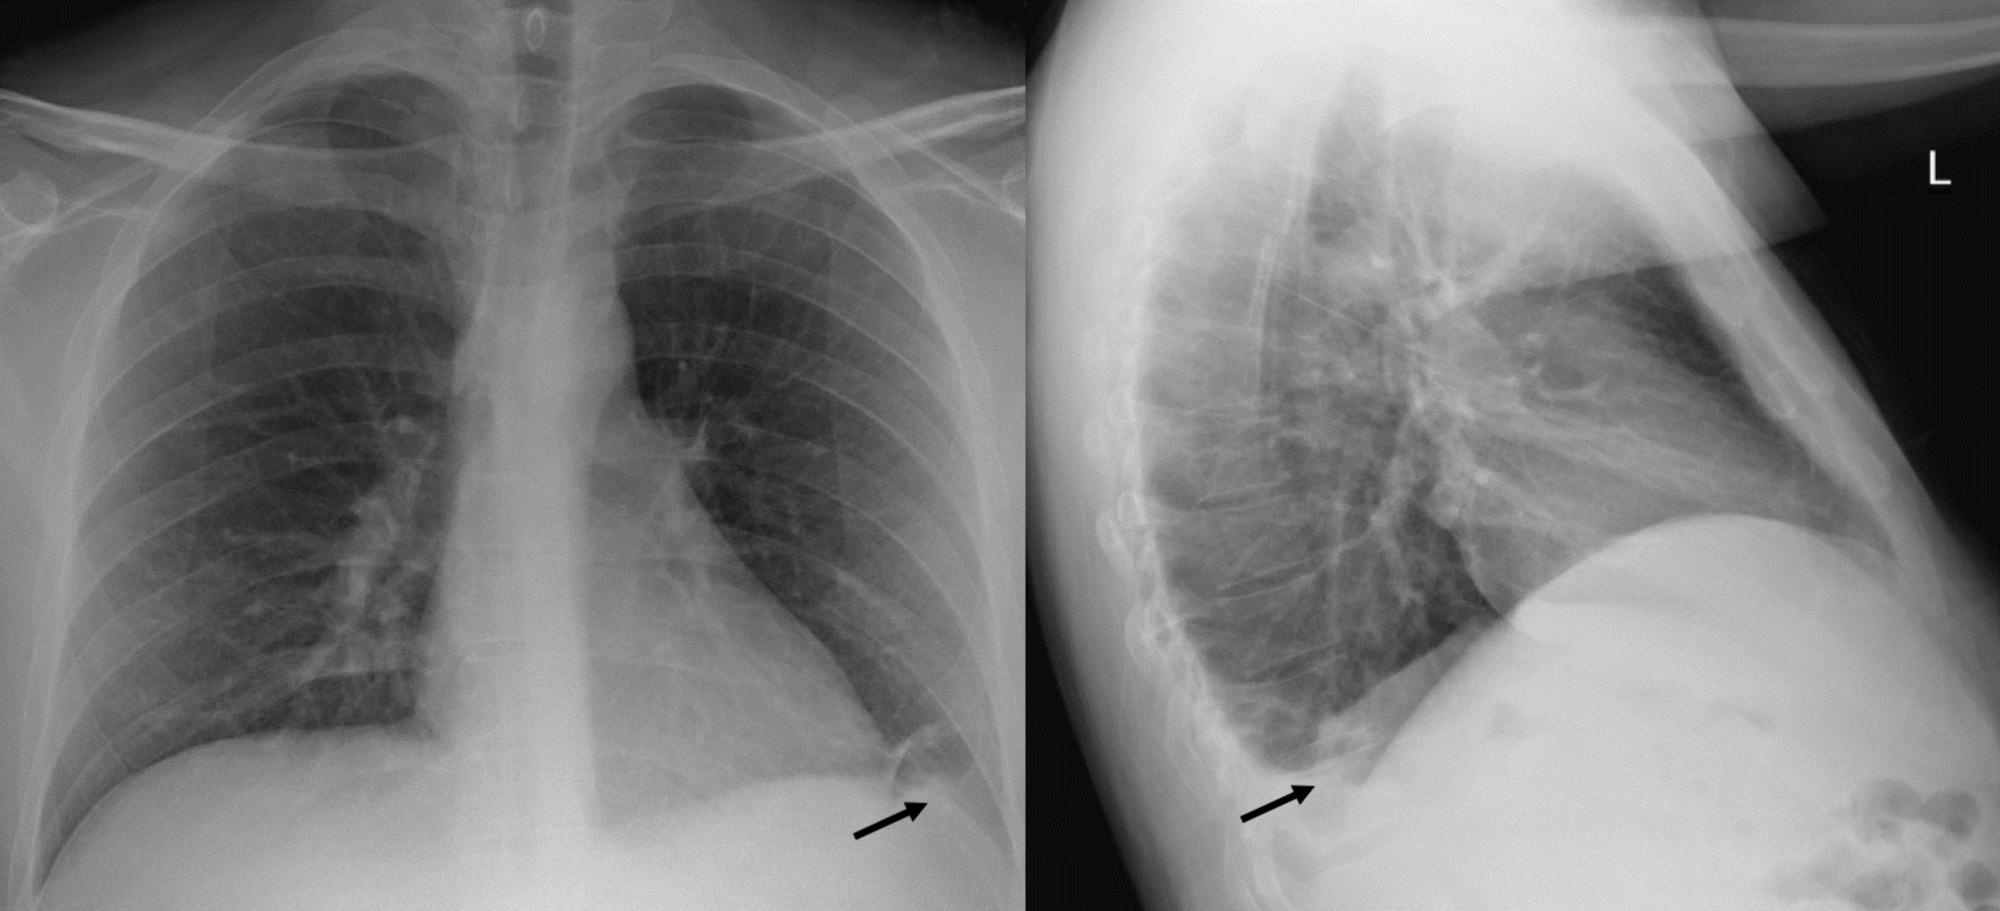

Chest Xray significant of a left basilar opacity (arrow), most likely What Does Basilar Opacity Mean It happens when the small air sacs called. Bibasilar atelectasis is a condition caused by a partial collapse of your lungs. 3 doctors weighed in across 2 answers. Pulmonary opacification represents the result of a decrease in the ratio of gas to soft tissue (blood, lung parenchyma and stroma) in the. What Does Basilar Opacity Mean.

Chest xray upon admission shows a small left basilar opacity (black What Does Basilar Opacity Mean It happens when the small air sacs called. Bibasilar atelectasis is a condition caused by a partial collapse of your lungs. 3 doctors weighed in across 2 answers. Pulmonary opacification represents the result of a decrease in the ratio of gas to soft tissue (blood, lung parenchyma and stroma) in the. What Does Basilar Opacity Mean.